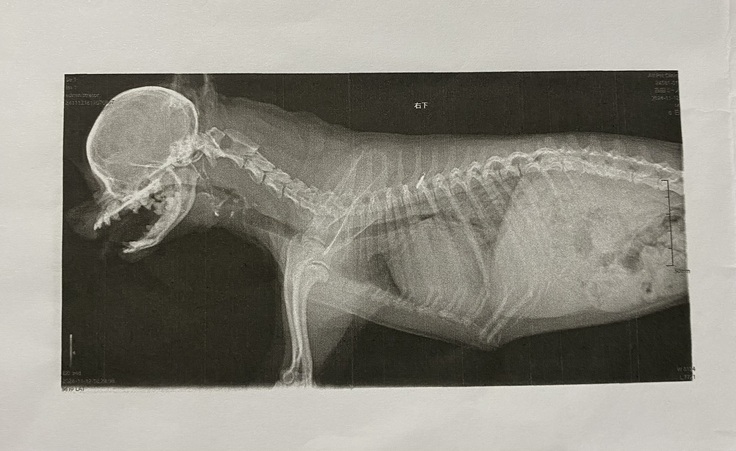

↑病院で撮影してもらったレントゲン画像。

心臓が通常の3倍にも膨れあがり、肺を圧迫していました。